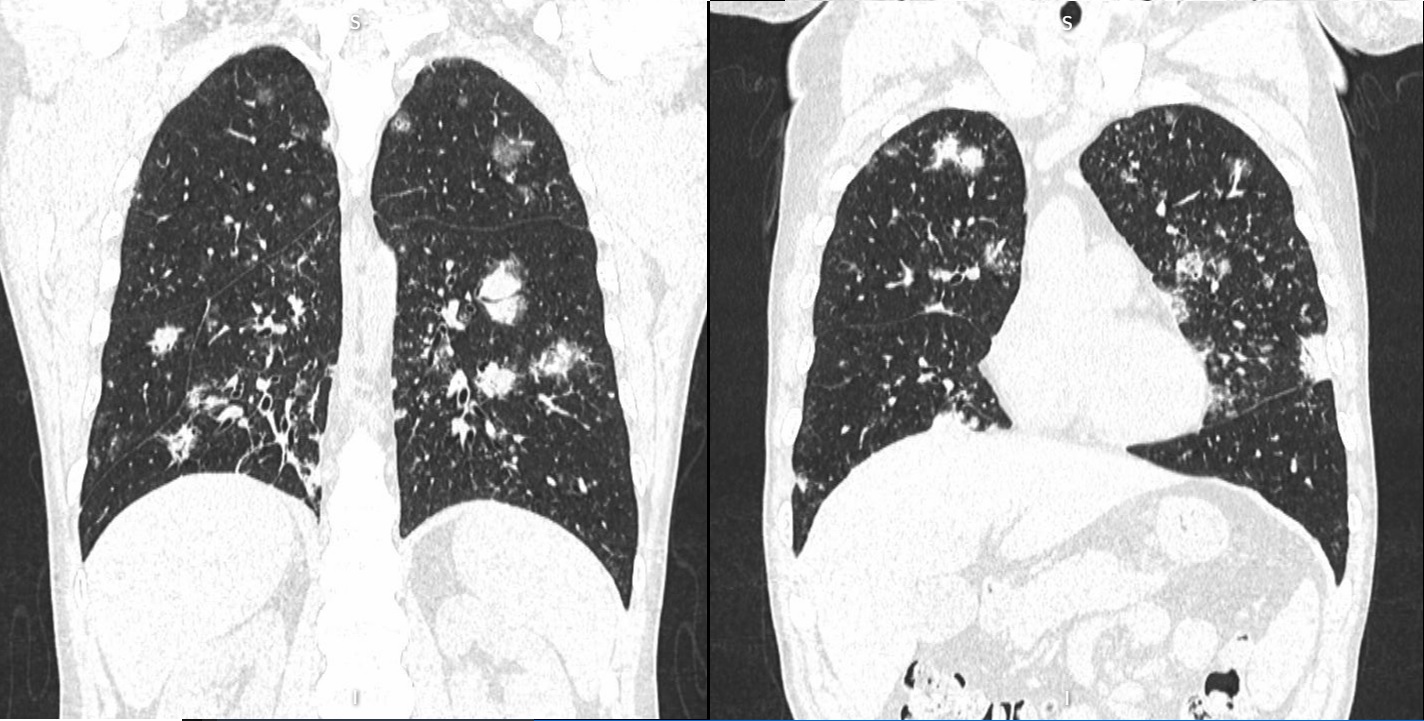

Case presentation: A 39-year-old man was initially diagnosed with lung cancer based on computed tomography and histopathologic findings. He was treated with 2 lines of chemotherapy over an 8-month period, the neoplastic lung lesions progressed, and he was referred to palliative care. Two years after his initial diagnosis, during the management of an actively bleeding gastric tumor, he was diagnosed with HIV and referred to an infectious disease unit. Immediate antiretroviral treatment was initiated after diagnosis, and further evaluation confirmed the presence of B-cell lymphoma. A retrospective review suggested that the initial cancer diagnosis was likely misinterpreted and was in fact lymphoma, a malignancy commonly associated with HIV. Lymphoma treatment was initiated, and after 1 year, the patient achieved HIV-1 virologic suppression and near-complete remission of all lesions.